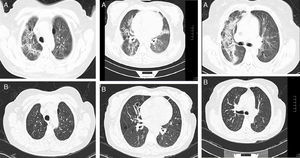

We had the initial HRCT of 33 patients, of these, 4 (12%) had a usual interstitial pneumonia (UIP) pattern, 12 (38%) had nonspecific interstitial pneumonia (NSIP) pattern and 17 (50%) had an indeterminate pattern with diffuse ground glass and reticulation images (Figs. 1 and 2). The median of the Kazerooni fibrosis scales was 0.47 and the median of the Kazerooni ground glass scale score was 2.33 (Table 3). We compared the response in the FVC at 6 months of follow up between patients with a value <0.47 of the fibrosis Kazerooni scale and those who had higher values. Those with lower Kazerooni scores (<0.47) were the ones who had a significant improvement in the FVC values (Table 4).

Representative CT images of RA-ILD patients. (A) Cystic lesions of subpleural and basal distribution resembling those seen in usual interstitial pneumonia, associated with areas of ground glass. (B) Ground glass with central distribution, respecting subpleural areas and discrete reticulation, resembling the pattern observed in the nonspecific interstitial pneumonia. (C) Reticulation and ground glass diffusely distributed, broncocentric, being an indeterminate pattern of interstitial lung disease.